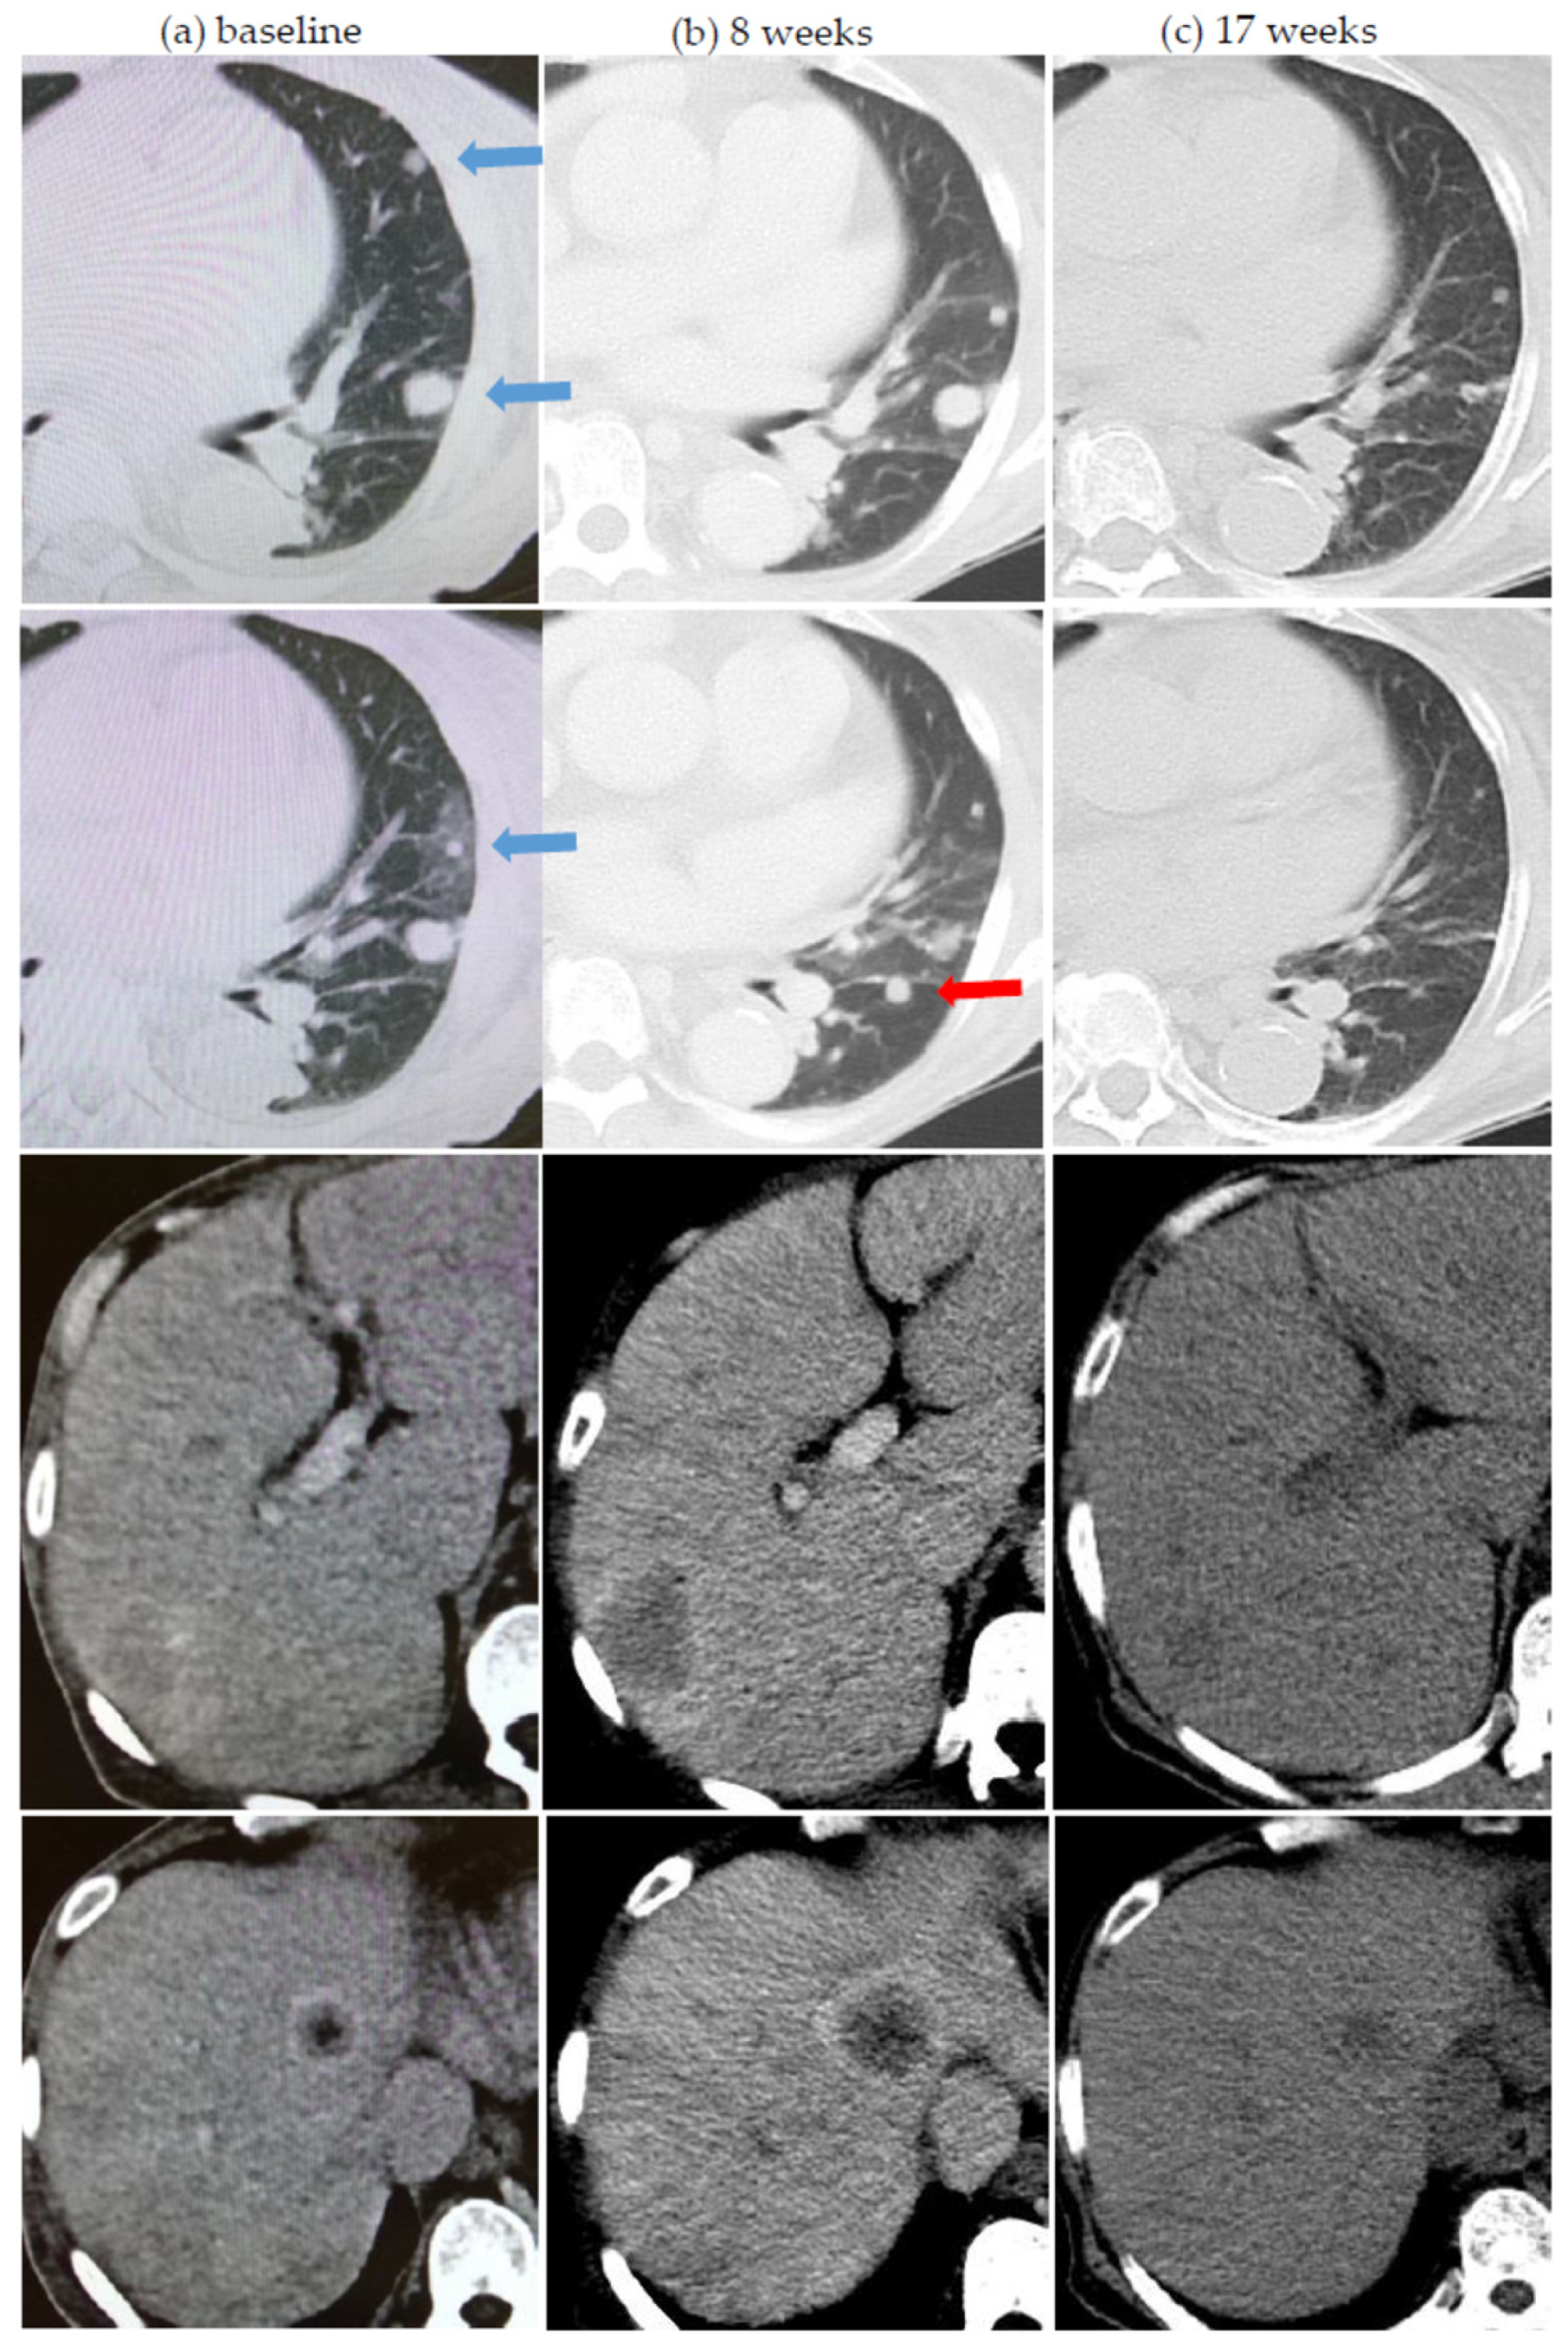

| 6 | Nivolumab | 17 26 | 54Gy/3 42Gy/5 25Gy/5 | Yes Yes | Lung Lung | Lung, 2 Lung, 2 | 5 3 | Prior spontaneous regression and dissociated response after cytoreductive nephrectomy |